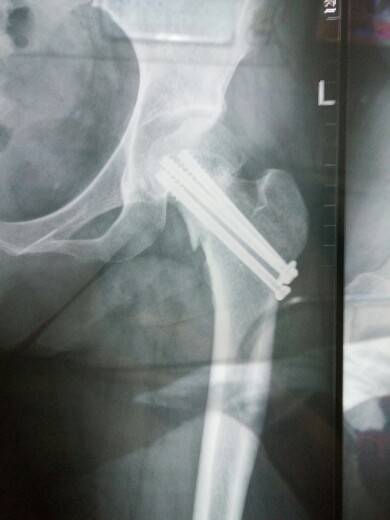

医生看见了,说助行器拿起,不能这样,心里知道我把问题看的太轻,我还没有恢复到可以走路的程度。上上个星期才照的片,骨折处的断裂还清晰,我知道骨头没有完全愈合,不能不重视,任性而为,同时还得安下心继续得它慢慢愈合,不能心急,也就是继续住院,不过还好,反正已经做好住到过年后的准备。

那是打了螺丝钉吗?看起来好怕啊!听医生的话吧!